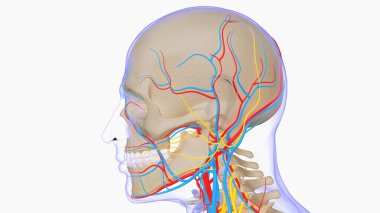

The arterial blood supply to the neck (carotids and vertebral arteries).

İnsanBaşıkanİlaçyüzboğazıBoyunresim çalışmasıprofilNormalbeyinarterkarotidKan damarıKan dolaşımıİnsan AnatomisiSerebral kan dolaşımıvaskülarizasyonsubclavian arteryortak Karotis arterbrachiocephalic Arteryel gövdeVertebral arterfacial arteryserebral artercervical arterytemporal arterydahili şah damarıharici şah damarıdeep cervical arteryBenzer İçerikler